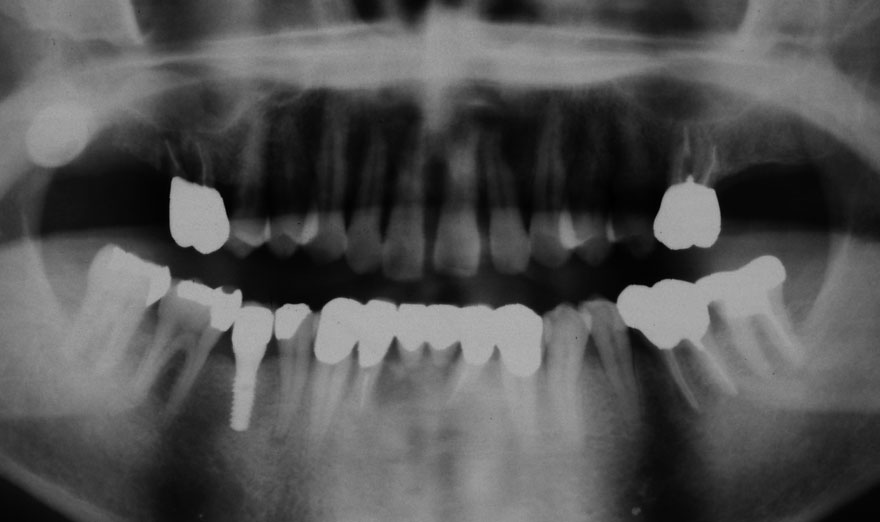

初診時 42歳 男性 平均歯槽骨喪失量:5.30mm

22年後 64歳

平均歯槽骨喪失量:5.554mm

22年間喪失量:-0.24mm

年間喪失速度:-0.01mm

(ケア頻度:1.07ヵ月ごと)